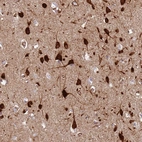

Immunohistochemical staining of human colorectal cancer shows moderate cytoplasmic positivity in tumor cells.